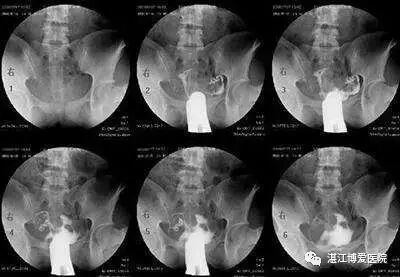

最常用的是输卵管造影(HSG)

医生会根据不孕的时间、可能的原因,来选择是否需要做HSG。

造影的时间一般在月经干净后3天到排卵之前,造影前不要有性生活,白带检查正常等等。造影后1周禁性生活,当月最好不要尝试怀孕。

不过现在的造影剂比较先进,一般代谢很快,假如不小心当月怀上,多数也没有问题。保险一点,等下次月经来过再试孕。